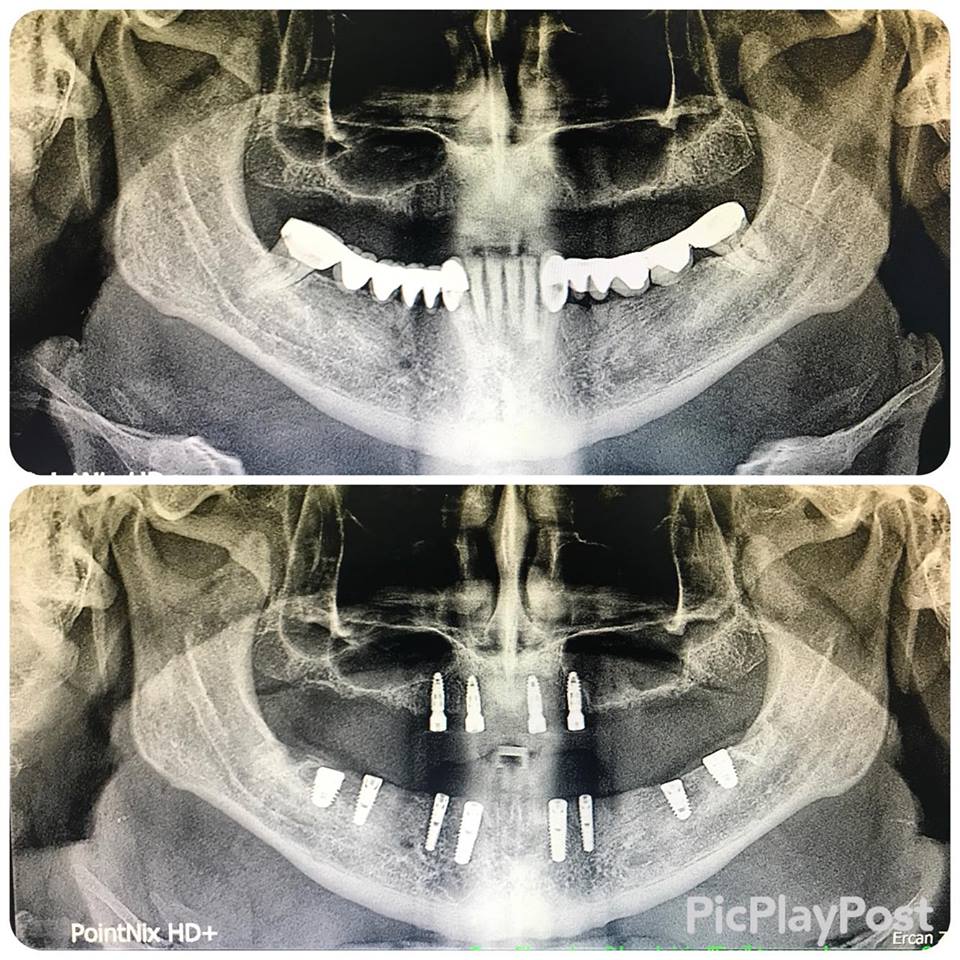

İMPLANT TEDAVİSİ

implant tedavisi